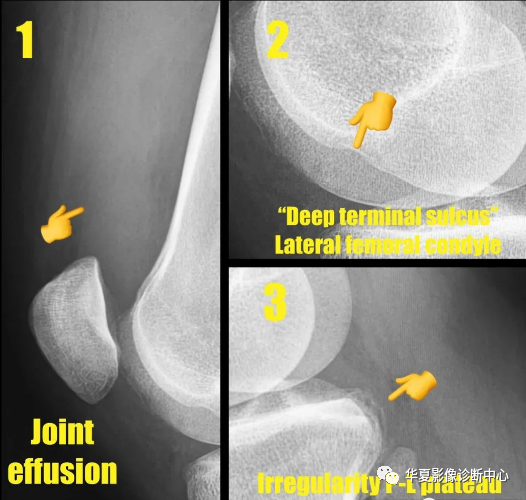

股骨外侧髁“深沟”征(Lateral femoral “notch” sign)

1-髌上囊积液、2-股骨外侧髁深沟征、3-后外侧胫骨平台损伤,共同征像表明轴移损伤机制